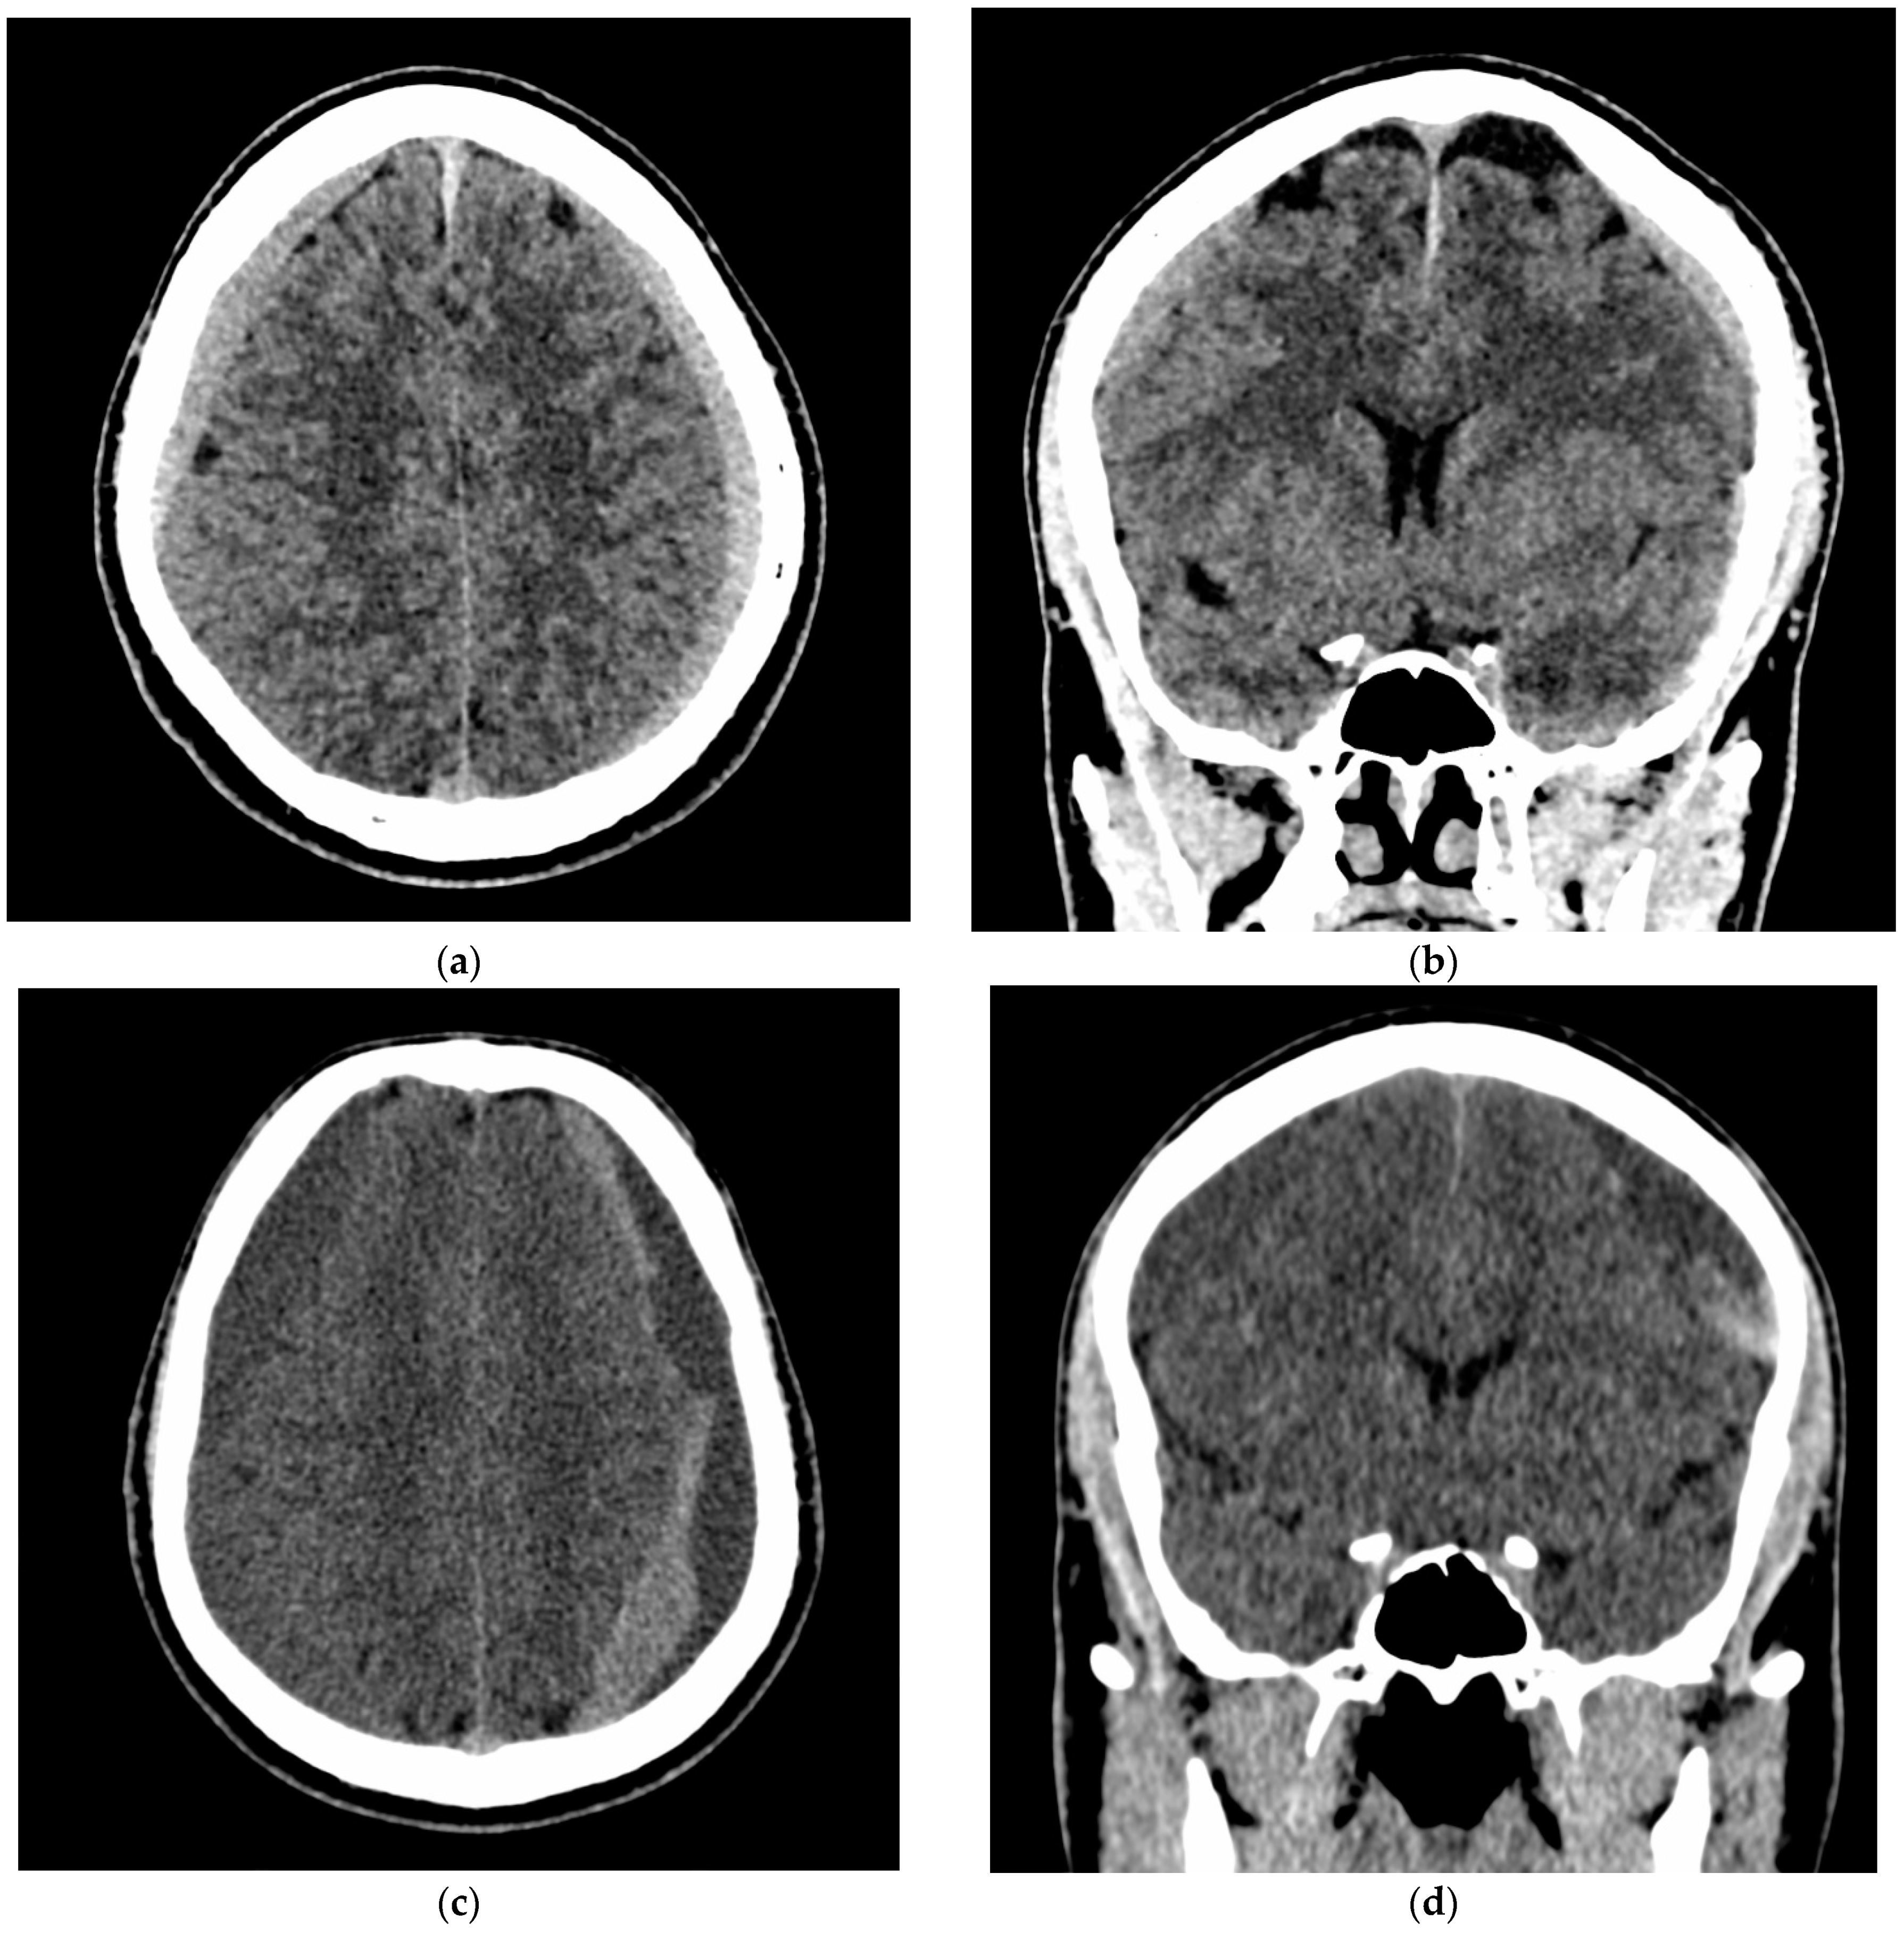

3.3.2. Efficacy Endpoint

3.4. Illustrative Cases